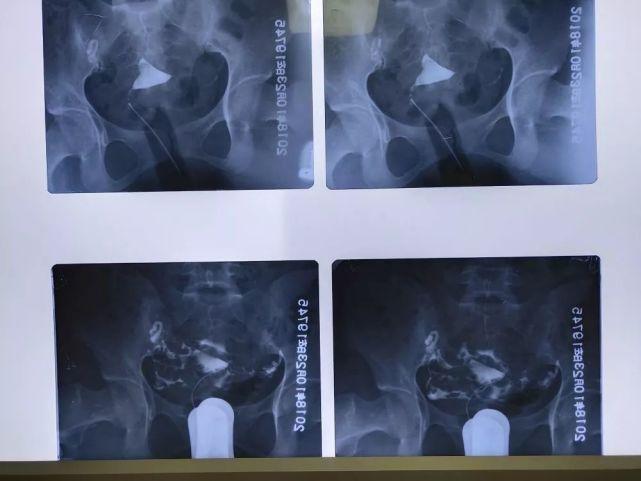

需要结合患者的病史,子宫输卵管造影等。

做该项检查主要是看输卵管是否通畅,有没有炎症。做输卵管造影的是子宫内膜的情况,宫腔内环境与胚胎着床位置。一般检查在子宫内膜至少需要1~3天才能显示输卵管畅通,子宫内膜的大小也不同。